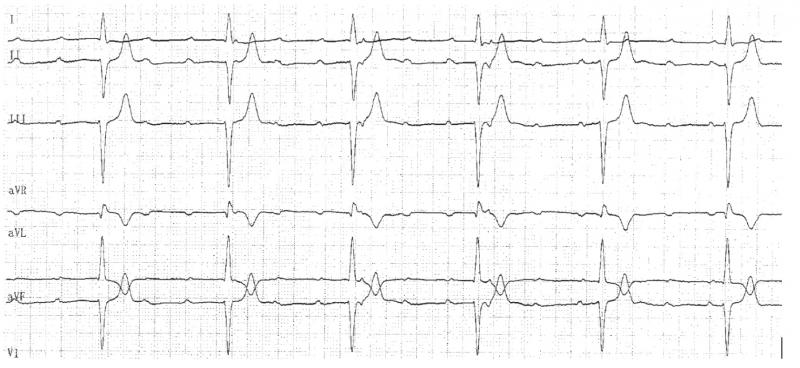

Fig 19 : Survenue inopinée d’une onde P bloquée. Il existe en RS un BBD et un HBAG avec un PR long. Il s’agit d’un BAV du second degré de type II. Il est plus grave car le témoin d’une atteinte bas située dans la jonction AV.

++++++++++++++++++++++++++++